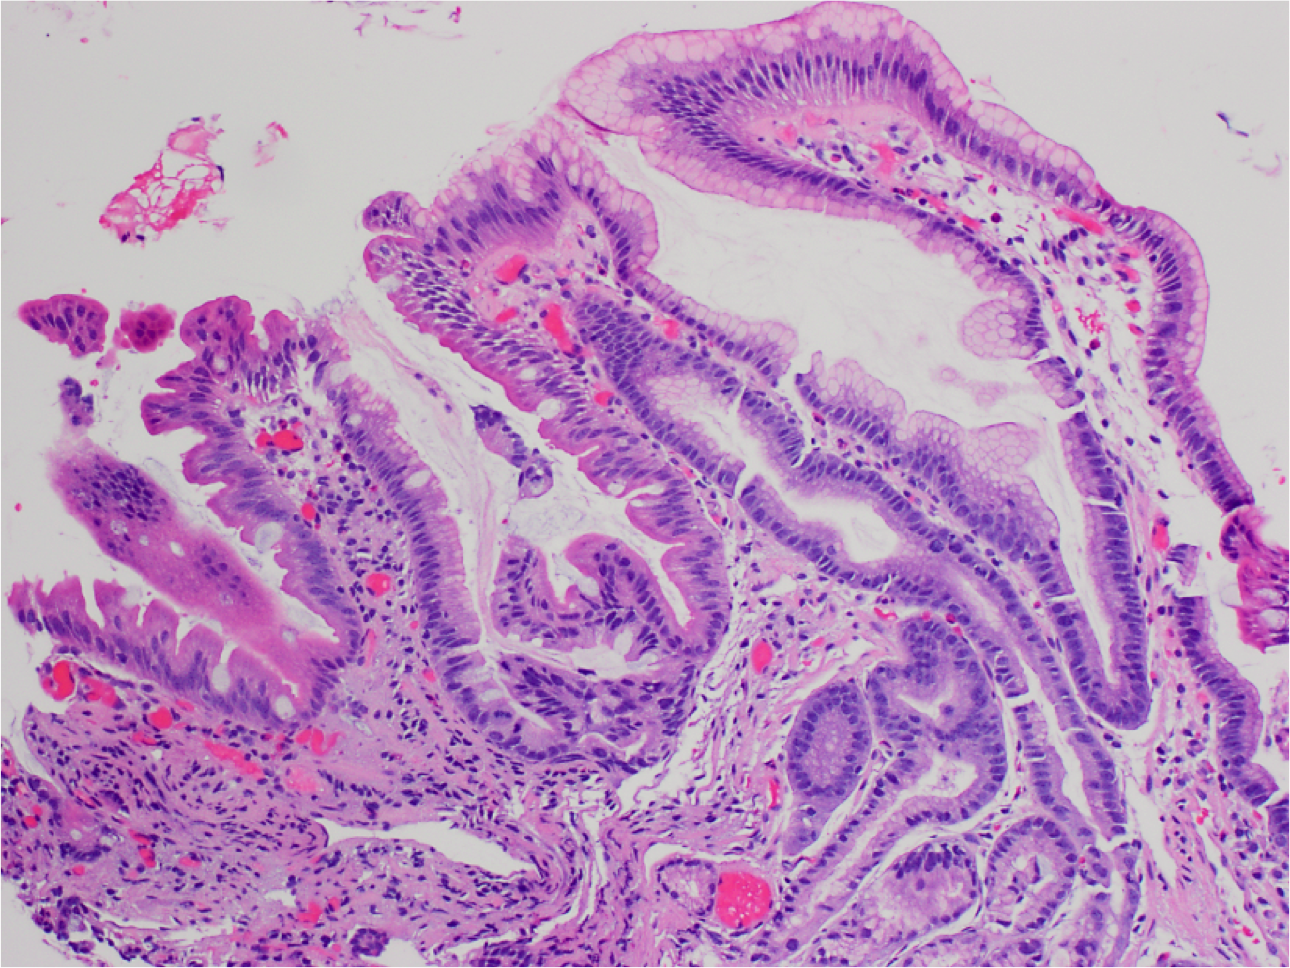

What’s this? What’s notable?

Barrett Esophagus.

Gastro-esophageal junction with columnar mucosa of intestinal type (intestinal metaplasia).

Goblet cells are present – note cells with large droplets of grey/blue mucin.

Also note maturation (increasing N:C ratio) of intestinalized epithelium towards the luminal surface of the crypts.